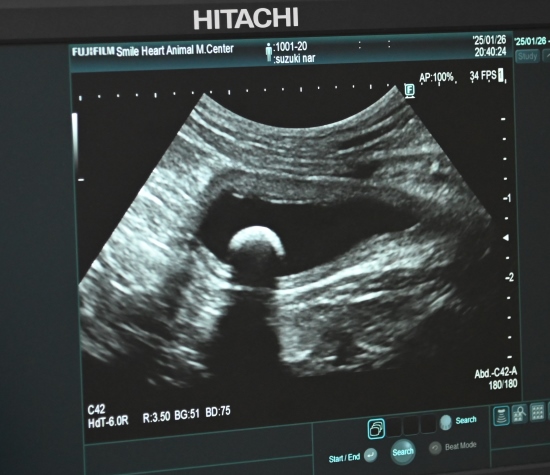

膀胱のエコー

エコーで、膀胱の中に、闇夜の月のように写っているのは、結石。

大きさは、7.6mmと、結構な大きさ。

実は、以前から膀胱の中に結石があることは判っていましたが、採尿ができなかったので、ストラバイト結石なのか、シュウ酸カリシウム結石なのかが判らず、先ずは、ストラバイト結石と仮定して食事療法で溶けるかどうか、様子を見る事にしており、正に、来週、通院予定でした。

で、本日の結果は、結石が溶けたり小さくなるどころか、大きくなっていることから、これは、シュウ酸カリシウム結石であることが、ほぼ確定。

血液検査の結果も、白血球と炎症反応の数値が異常値となっており、石が膀胱内で動いて、膀胱の内壁を傷つけている可能性もあり、外科手術で、結石を除去することになりました。

本日は、皮下補液、鎮痛剤、抗生剤、ビタミン剤などの注射を行い、近々、手術の予定です。